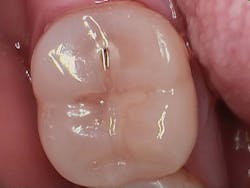

Figure 1 shows a large radiolucency on the mesial and a small radiolucency on the occlusal of tooth 31. Figure 2 shows an initial caries lesion on the distal pit and a leaking occlusal composite. Tooth 31 was sensitive to cold but normal to chewing, bite, and heat. Selective caries removal was used to prevent pulp exposure and preserve the marginal ridge.